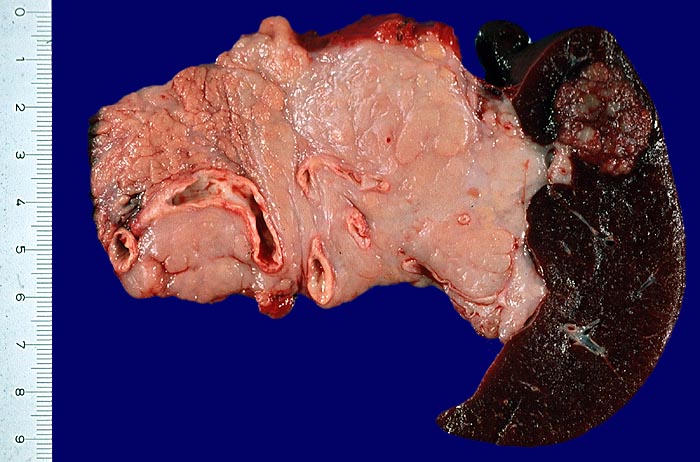

Das Hodgkin-Lymphom befällt primär lokal eine Lymphknotengruppe, meist des Halses und breitet sich entlang des lymphatischen Gewebes aus. Bei nodulärer Sklerose (ca 70% aller cHL) findet sich in den meisten Fällen eine mediastinale Tumormasse.

Makroskopie

Befund

Pathologischer Befund